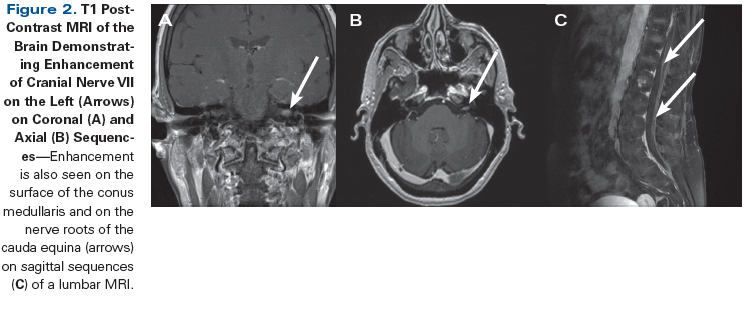

Figure 2. T1 Post-Contrast MRI of the Brain Demonstrating Enhancement of Cranial Nerve VII on the Left (Arrows) on Coronal (A) and Axial (B) Sequences

A 65-year-old woman with non−small-cell lung cancer diagnosed 11 years earlier (stage IB at diagnosis) developed bony metastases 1 year prior to the current presentation. A thoracic vertebra metastasis was treated with focal radiation therapy (RT; 60 Gy). Later on, the patient developed unilateral facial weakness. Her symptoms were initially thought to represent idiopathic Bell’s palsy, but remained refractory to treatment with steroids and acyclovir. Brain MRI at that time demonstrated ipsilateral cranial nerve VII enhancement (Figure 1). Her CSF was noninflammatory, without evidence of malignant cells. Subsequently, over a 4-month period, the patient developed bilateral facial weakness, unilateral tinnitus, dizziness, hyperacusis, and abnormal sensations in the right upper extremity. Electromyography and nerve conduction studies of facial nerves revealed an axonal degenerative process, without evidence of demyelination. Repeat CSF studies demonstrated lymphocytic pleocytosis with malignant cells on cytology, and a diagnosis of leptomeningeal carcinomatosis was made. An MRI of the spine revealed nodular enhancement at the conus medullaris.

Classic radiographic findings of neoplastic meningitis include the presence of enhancement between cerebellar folia, deep in the brain sulci, and over the convexities. Enhancement can also be present on the surface of the spinal cord or on the nerve roots of the cauda equina. However, these findings are nonspecific and can also be seen in infectious diseases (tuberculosis, for example) and autoimmune conditions (sarcoidosis, for example), and oftentimes as an artifact following lumbar puncture. Thus, the timing of radiographic evaluation and lumbar puncture is important: imaging should always precede spinal tap whenever possible. It should be emphasized that radiographically evident disease may not always be symptomatic in patients with leptomeningeal carcinomatosis. The wide range of reported negative imaging in the setting of positive CSF findings (30% to 70%) arises at least in part from the varying methodologies utilized to evaluate the incidence of leptomeningeal carcinomatosis.[6] The explanation for negative CSF studies in the setting of abnormal imaging suggestive of leptomeningeal carcinomatosis may be even less clear. This may be due to some patients being diagnosed with leptomeningeal carcinomatosis radiographically and not being optimal candidates for lumbar puncture due to noncommunicating hydrocephalus, large intracranial metastases, thrombocytopenia, or other medical issues.

A 40-year-old woman with a history of stage IV carcinoma of the breast with diffuse bony metastases (ypT4N3M1, infiltrating ductal carcinoma, grade 2, estrogen/progesterone receptor–positive, human epidermal growth factor receptor 2 [HER2]–negative at diagnosis) was treated with mastectomy, hormone therapy, and RT. Three years after her initial cancer diagnosis, she developed complex partial seizures (episodes of left head deviation, speech arrest, and staring lasting 1 to 2 minutes) and confusion. Her neurologic exam did not demonstrate any new focal deficit, but the patient did acknowledge shooting pains with neck flexion. Seizures were treated with the non–enzyme-inducing anti-epileptic medications (AED) levetiracetam and lacosamide. A brain MRI demonstrated ventriculomegaly and enhancement within sulci along both the frontal and parietal lobes (Figure 2). CSF cytology demonstrated metastatic cells, and a diagnosis of leptomeningeal carcinomatosis was made.